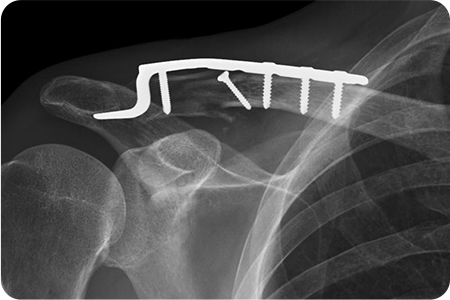

X-ray 및 CT를 통해 골절 형태와 전위 정도를 확인합니다.

골절된 뼈를 원래 위치로 맞추는 정복 작업을 진행합니다.

금속판, 나사, 고정막을 이용해 뼈를 고정합니다.

쇄골 위쪽을 따라 약 5~8cm 정도 절개하여

골절 부위를 노출합니다. 정복과 고정을 시행하고

절개 부위를 봉합합니다. 수술 후 일정 기간 동안

팔의 움직임을 제한해 뼈가 안정적으로 붙도록 합니다.

골절·외상 수술은 손상된 뼈와 조직을 정밀하게 맞추고 금속판·나사·핀 등을 이용해 안정적으로 고정하는 치료입니다.

이 과정에서 뼈의 정렬과 관절 기능을 회복하기 위한 섬세한 판단이 필요하기 때문에,